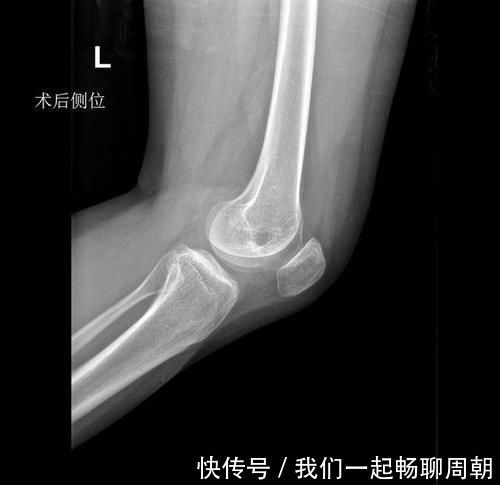

x光片|左边膝盖疼了1年多,结果查出来这一系列问题

今年21岁的小程,正在广州读大三,一年前小程在参加运动会时伤到了膝盖,本以为稍作休息就能有所缓解,但是左膝疼痛断断续续维持了一年多,直到最近一个月病情越发严重。

通过一系列的检查,前十字韧带松弛(左膝关节前交叉韧带损伤)、陈旧性膝外侧副韧带损伤(左侧)、滑膜炎(左膝)、膝关节积液(左侧)、左胫骨平台囊肿。

在排除了手术的禁忌症的情况下,我们为小程做了左膝关节镜检治疗术,术中见:

1)关节腔内滑膜轻度增生、充血。

2)探查左膝内、外侧半月板,可见外侧半月板轻度磨损,外侧半月板边缘毛糙,但无明显撕裂;内侧半月板未见明显损伤。

3)股骨外侧髁软骨面未见明显损伤;股骨内侧髁软骨面可见软骨软化,内侧髁外侧可见轻度磨损。

4)探查前、后交叉韧带、腘肌腱,可见后交叉韧带股骨侧止点变异,偏向于软骨侧,前后交叉韧带距离较近,相互摩擦,前交叉韧带部分损伤,剩余部分张力可,探查可见轻度松弛,考虑无需行前交叉韧带重建。

5)探查膝关节腔,髁间窝较正常狭窄约3-5mm左右。予以刨刀清理关节腔内增生、充血的滑膜组织。